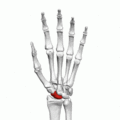

![]() Left hand anterior view (palmar view). Scaphoid bone shown in red. | |

The scaphoid bone /ˈskæfɔɪd/ (from the Greek word scaphoides, boat-shaped) is one of the carpal bones of the wrist. It is situated between the hand and forearm on the thumb side of the wrist (also called the lateral or radial side). It forms the radial border of the carpal tunnel. The scaphoid bone is the largest bone of the proximal row of wrist bones, its long axis being from above downward, lateralward, and forward. It is approximately the size and shape of a medium cashew.

The scaphoid is situated between the proximal and distal rows of carpal bones. It is located on the radial side of the wrist, and articulates with the radius, lunate, trapezoid, trapezium and capitate.[1] :176 Over 80% of the bone is covered in articular cartilage.[2]